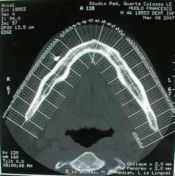

Il paziente, nel Marzo del 2007, si sottoponeva a visita

Odontoiatrica, per un eccesivo gonfiore da granuloma apicale dell’elemento 45 in arcata inferiore, si richiedeva una Tc. Dentascan( foto 2-3-4-5) per una migliore diagnosi radiologica;

foto 2 -3 tc dentascan

Dal referto del Radiologo si diagnosticava: nella sede del 44 inferiore, si apprezza formazione osteolitica rotondeggiante con diametro di 1 cm. riferibile a granuloma apicale;

In sede del 45, nell’ambito dei tessuti molli, nel versante vestibolare, si apprezza formazione rotondeggiante iperdensa

verosimilmente metallica localizzata nell’ambito dei tessuti molli, con diametro di circa 6mm.